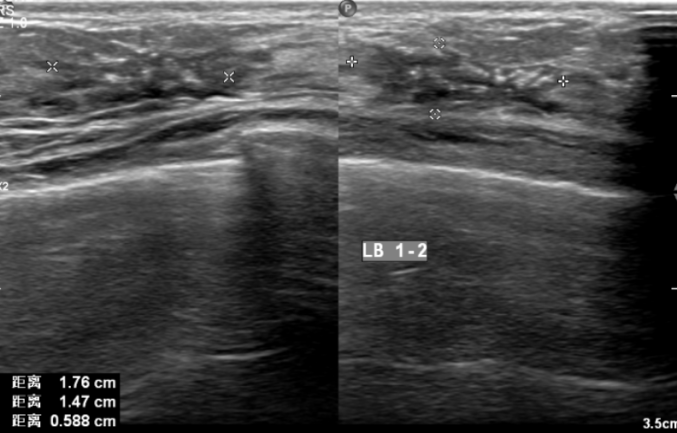

2021.9.9乳腺B超提示:左侧乳腺1-2点钟A环内见大小约18*15*6mm低回声区,边界不清,内见散在强光点,周边可见血流信号。余双侧乳腺腺体形态、结构未见异常。

两侧腋窝可见多枚低回声结节,边界清,有包膜,左侧较大者约9*5mm,右侧较大者约10*4mm,血流信号不明显。

影像诊断:左侧乳腺低回声区(BI-RADS:6类);两侧腋窝多枚淋巴结显示。

图4.乳腺B超(2021-9-9)